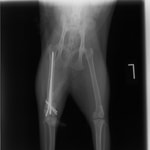

術後レントゲン